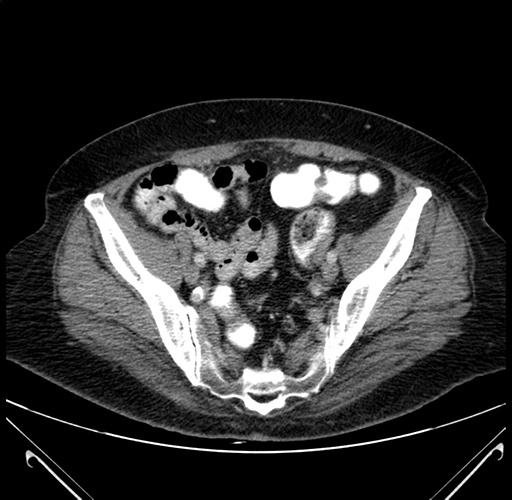

Pre-Chemo: Coronal Venous

Coronal Venous